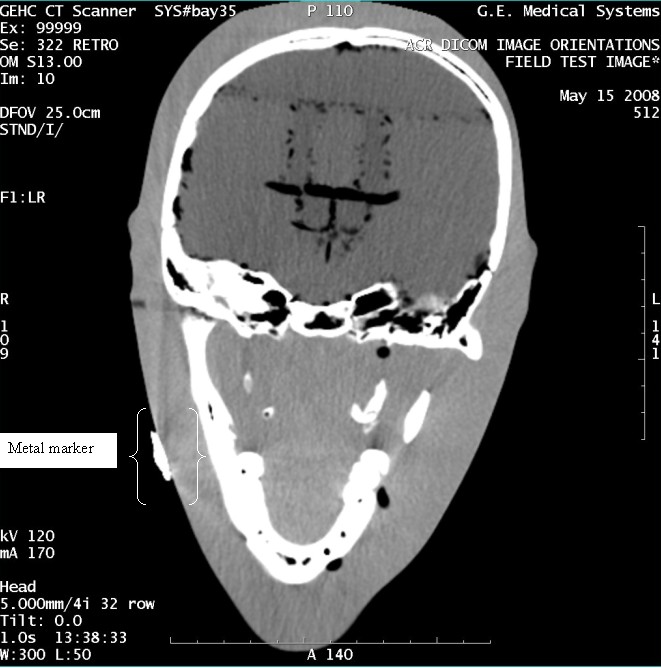

- With the support of the site personnel, examine the images sent

to the Review Station (i.e., 12 series, each with 1 image) and compare

their orientation to the images in this document.

- Each image contains a metal marker on the phantom's right cheek.

- Each image in this document contains a description of the expected

orientation of the metal marker (i.e. to prove Left and Right) as

well as the Posterior and Anterior orientation description.note:

The sample images included in this document use “R”, “L”, “P”, and “A” for “Right”, “Left”, “Posterior” and “Anterior” orientation. The Hospital Review Station may use a different style of annotation. The style used is not relevant to this procedure.

Figure 6. Exam 99999, Series 322